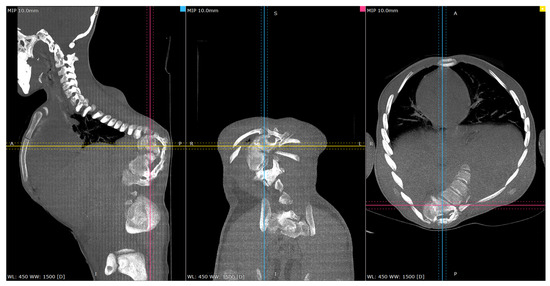

Figure 10.

Representative post-op CT scan views—4-months Post-operatively. Cross-reference grid lines mark the intersection of the corresponding image planes: Blue—sagittal; Pink—Coronal; Yellow—Axial view.